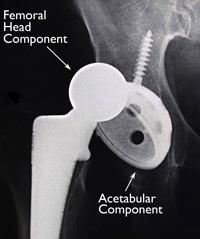

Many different types of designs and materials are currently used in artificial hip joints. All of them consist of two basic components: the ball component (made of highly polished strong metal or ceramic material) and the socket component (a durable cup of plastic, ceramic or metal, which may have an outer metal shell).

(Left) The individual components of a total hip replacement. (Center) The components merged into an implant. (Right) The implant as it fits into the hip.

(Left) A standard non-cemented femoral component. (Center) A close-up of this component showing the porous surface for bone ingrowth. (Right) The femoral component and the acetabular component working together.

(Left) The acetabular component shows the plastic (polyethylene) liner inside the metal shell. (Right) The porous surface of this acetabular component allows for bone ingrowth. The holes around the cup are used if screws are needed to hold the cup in place.

X-rays before and after total hip replacement. In this case, non-cemented components were used.